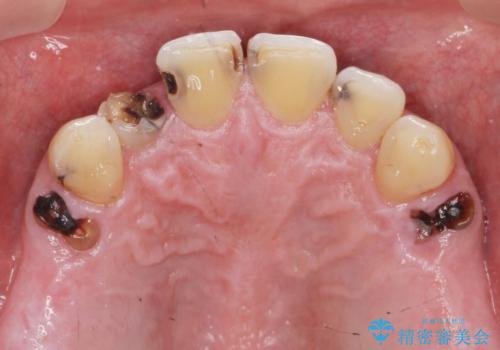

虫歯のマイクロスコープによる丁寧な除去、根管治療、深い虫歯に対する挺出(エクストリュージョン)および歯周外科を行ったのち精度の高いセラミッククラウン製作治療を計画します。

虫歯の放置により、根管治療や深い虫歯に対する処置が必要になりましたが丁寧に一つづつ処置を行ったことで抜歯をすることなく歯を残すことができました。

セラミッククラウンの製作をする前に、歯内・歯周環境の整備は非常に大切です。